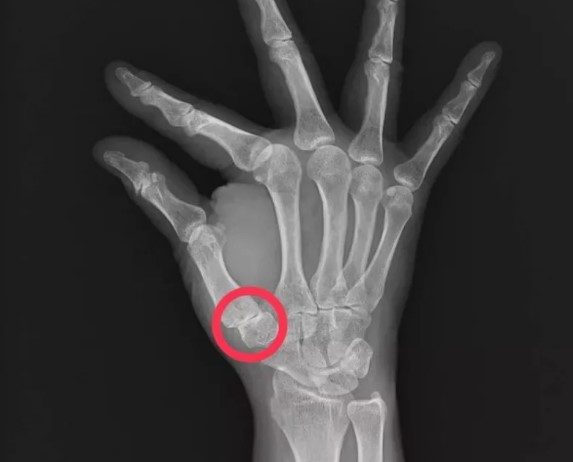

右手拇指掌腕關節空間縮小及骨刺形成,是拇指掌腕關節炎的典型影像表現。圖/大里仁愛醫院提供

拇指的腕掌關節由許多腕骨掌骨形成關節面,提供拇指極大的活動度及功能,包含伸、屈、抓、握、拿、捏。但高活動度的關節若使用過度,常使關節韌帶受損及軟骨磨損,進而造成骨刺與關節炎發生,令患者因生活大受影響而困擾不已。